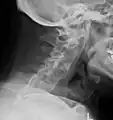

The earliest changes demonstrable by plain X-ray shows erosions and sclerosis in sacroiliac joints. Progression of the erosions leads to widening of the joint space and bony sclerosis. X-ray spine can reveal squaring of vertebrae with bony spur formation called syndesmophyte. This causes the bamboo spine appearance. A drawback of X-ray diagnosis is the signs and symptoms of AS have usually been established as long as 7–10 years prior to X-ray-evident changes occurring on a plain film X-ray, which means a delay of as long as 10 years before adequate therapies can be introduced.[26]

Lateral X-ray of the neck in ankylosing spondylitis